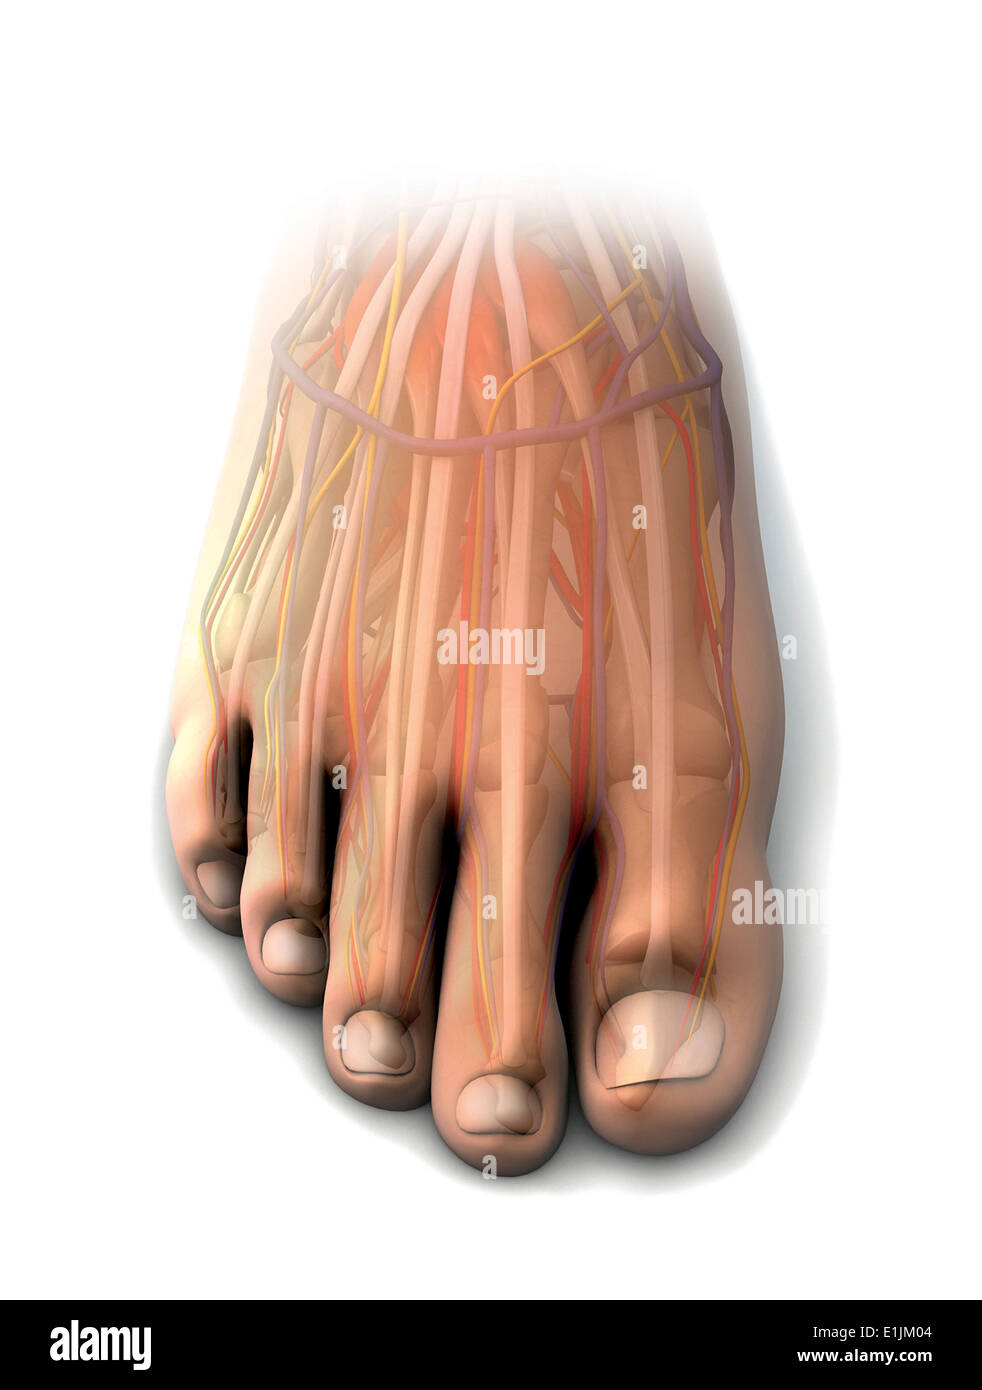

www.alamy.itIl Piede Umano Muscles L’anatomia Illustrazione Di Stock

www.alamy.itIl Piede Umano Muscles L’anatomia Illustrazione Di Stock

it.dreamstime.comanatomie anatomia piede muscles umano menselijke humain illustratie afbeelding

it.dreamstime.comanatomie anatomia piede muscles umano menselijke humain illustratie afbeelding